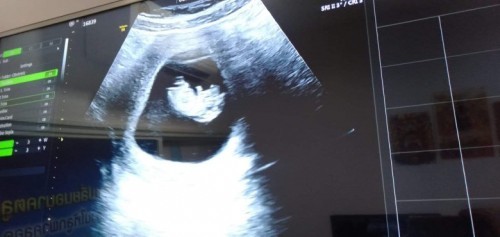

ขอสอบถาม 13สัปดาห์แล้วน้องยังไม่เป็นตัว คนอื่นเป็นเหมือนกันไหมคะ แต่หมอบอกหัวใจน้องเต้น กังวลคะ จะเป็นไรไหม

ซาวตอน13wค่ะก็เห็นแล้วนะคะ

บ้านนี้ 13wคะ เป็นตัวแล้ว